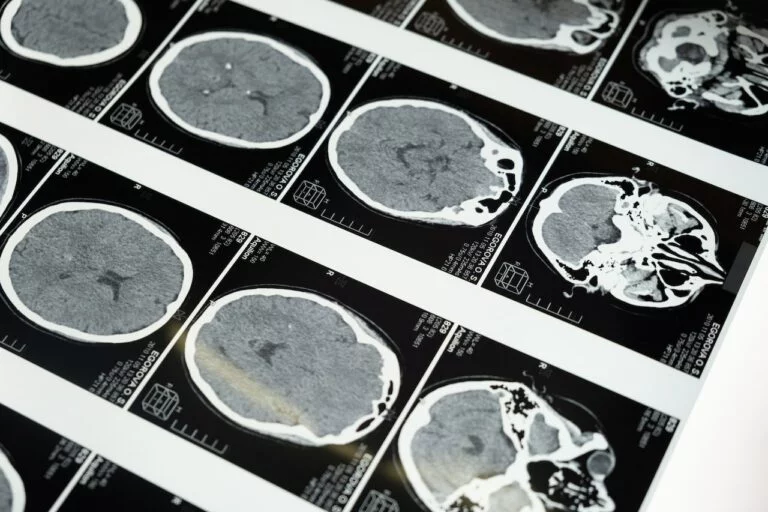

Neuralink è un dispositivo nato dal genio visionario di Elon Musk unitamente ad un team di esperti in campo scientifico, sanitario, psicologico e informatico, eredita il nome anche la stessa società di neuro tecnologia avanzate che si fa carico di tutte le attività del progetto. Neuralink sta lavorando ad una interfaccia neurale che possa far connettere il cervello umano con un elaboratore.

L’idea di base dovrebbe permettere alle persone affette da patologie neurali come la depressione, Alzheimer, epilessia e altri traumi collegati al sistema nervoso, di effettuare degli upload e download proprio come avviene per i software ma in questo caso si tratterebbe di scambio di dati tra neuroni contenuti in specifiche aeree celebrali e l’interfaccia elettronica di Neuralink.

Questa ambiziosa scommessa mira ad aprire una frontiera di scenari futuristici e innovativi in diversi settori tra i quali quello sanitario. L’anno 2020 è stato l’anno designato dalla società per presentare al mondo il progetto e iniziare la sperimentazione sull’essere umano, ed entrare nel mercato già per il 2022 si spera. La trasmissione dei dati tra cervello e periferica artificiale si basa su un sistema di trasduzione del sistema nervoso centrale umano di cui fa parte il cervello e il midollo spinale ove sono contenuti i neuroni che scambiano continuamente segnali chimici ed elettrici. Da tempo i ricercatori si sono adoperati nel cercare soluzioni tecniche che possano essere utilizzate per intercettare i segnali danneggiati e ripristinarli soprattutto nelle persone paralizzate che a causa di gravi incidenti o malattie sono rimaste inabilitate nelle funzioni primarie.